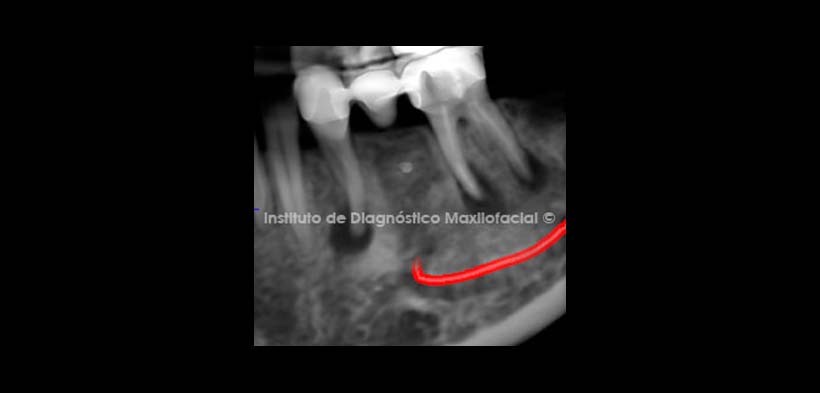

Se procedió a evaluar la reformación con cortes transversales para determinar, la morfología de la pieza dentaria 4.4 además de la lesión apical, también se evaluara la pieza dentaria 4.6  donde se observa una posible raíz supernumeraria con dos posibilidades (radix entomolaris o radix paramolaris). Fig.2

Se realizaron cortes transversales a nivel de los conductos radiculares de la pieza dentaria 3.6 pudiendo evidenciarse la presencia de un RADIX ENTOMOLARIS obturado, además del aumento de la densidad ósea circundante y presencia de lesiones apicales en raíz mesial y distal.  (Fig. 6, 7, 8, 9, 10).